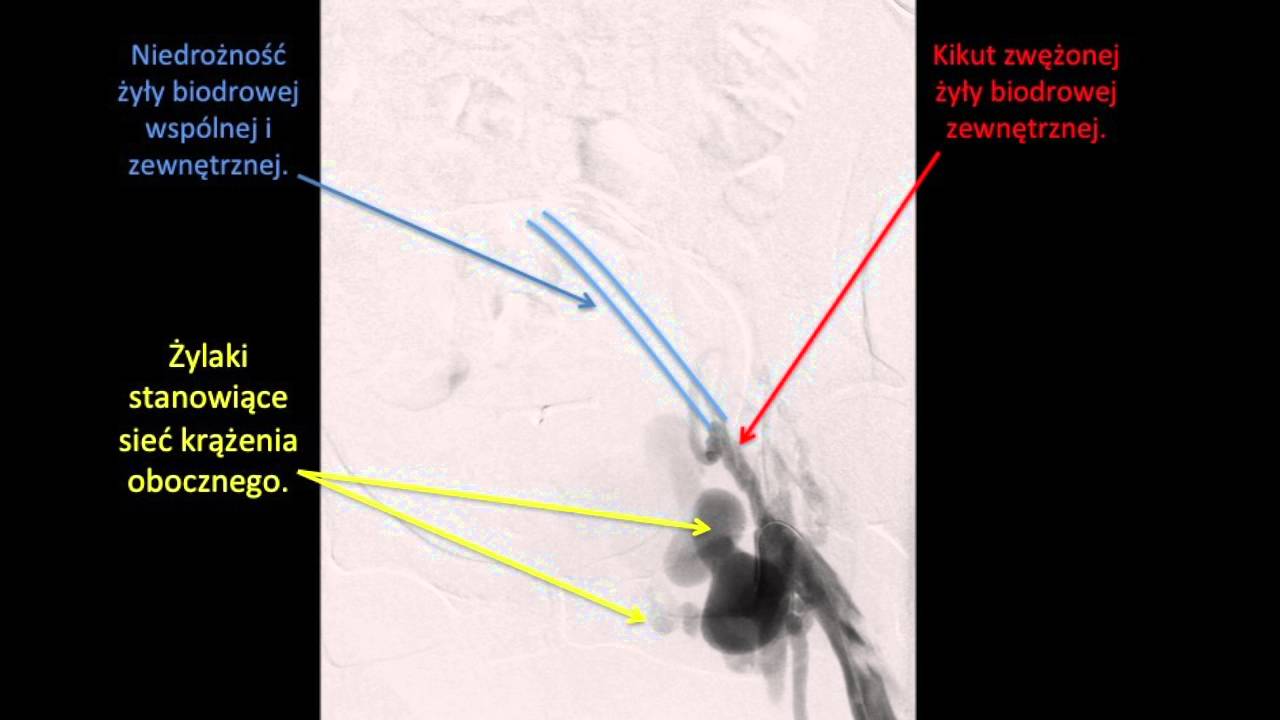

Przyczyna obrzęku lewej kończyny nie zawsze jest oczywista. Nawet rutynowe badania dopplerowskie nie zawsze pozwalają na postawienie trafnej diagnozy. Może to wymagać pogłębionego badania USG doppler żył biodrowych a czasem nagio-MR lub wewnątrzżylnego badania USG czyli IVUS. Zapraszam na wizytą a w międzyczasie do zapoznania się artykułem poświęconym temu zagadnieniu, niestety nie ma tu możliwości wklejenia linku, proszę wpisać w wyszukiwarkę: Obrzęki nóg - dlaczego lewa noga puchnie częściej?